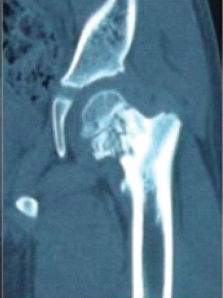

Coxa Vara of Unknown Etiology: A Unique Case Report

M Vignesh Velavan , J K Giriraj Harshavardhan

………………………………p.201-206